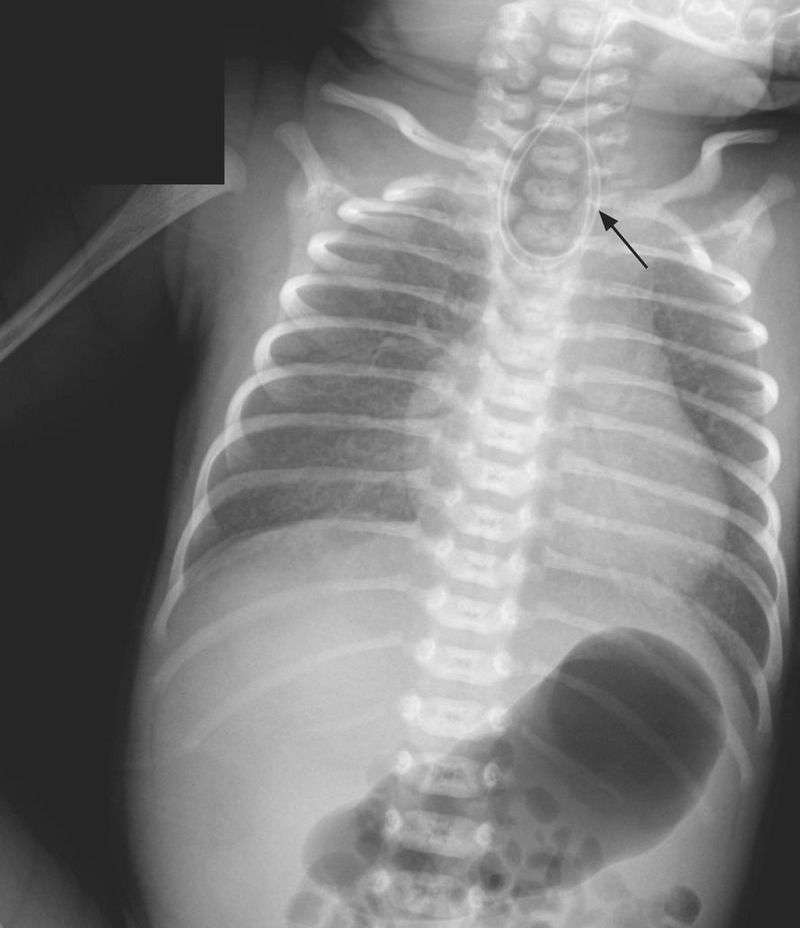

An infant had an apneic episode at birth and received positive-pressure ventilation in the delivery room during neonatal resuscitation. The infant had a birth weight of 2400 g (5th percentile) and was born to a 39-year-old woman who had presented for a planned cesarean section at 37 weeks 2 days of gestation. The prenatal course had been complicated by obesity, poorly controlled gestational diabetes, and polyhydramnios. Prenatal ultrasonography had not revealed fetal abnormalities. The Apgar scores were 1 point at 1 minute and 9 points at 5 minutes. Owing to the infant’s copious oral secretions, a nasogastric tube was inserted but met resistance at 11 cm. A chest radiograph showed the catheter coiled in the esophagus (arrow) at the level of the second thoracic vertebra and air in the stomach. Esophageal atresia with tracheoesophageal fistula, type C, was diagnosed. Type C, the most common type, is characterized by a proximal esophageal pouch with a distal tracheoesophageal fistula. Esophageal atresia and tracheoesophageal fistula may be associated with congenital vertebral, anorectal, cardiovascular, renal, and limb defects (collectively known as the VACTERL association). Physical examination, echocardiography, and renal ultrasonography did not reveal associated abnormalities. Primary esophagoesophagostomy and ligation of the tracheoesophageal fistula were performed on day 2. The patient began feeding by mouth on day 9 and was discharged on day 33. At follow-up visits at 2, 4, and 6 months of age, the infant was growing and developing well.